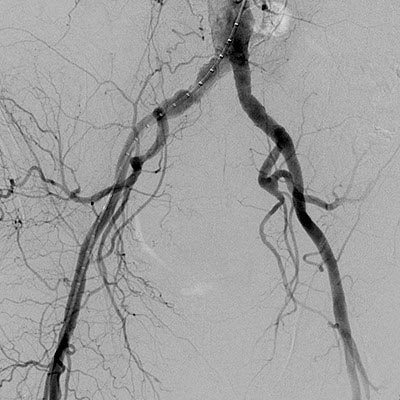

La arteria femoral superficial es el vaso que se ocluye con mayor frecuencia por ateroesclerosis. Las lesiones a menudo se ubican en el sitio donde la arteria femoral superficial pasa por…

Las lesiones ateroescleróticas oclusivas que se desarrollan en las extremidades, o arteriopatía periférica, son signos de un proceso ateroesclerótico sistémico. La prevalencia de la arteriopatía periférica es de 30% en…